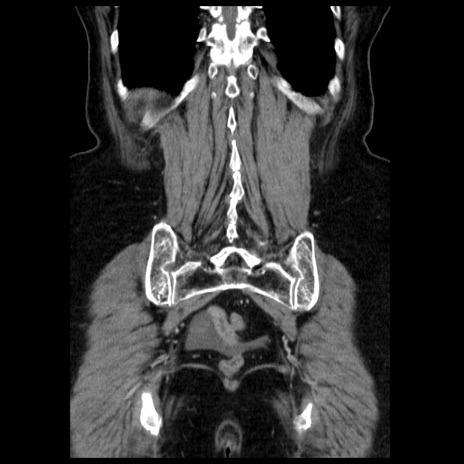

症例13(冠状断像)

【症例】70歳代女性

【主訴】腹痛、嘔吐

【現病歴】15時間程前(昨晩)より腹痛あり。今朝になっても症状の改善なく、嘔吐あり。腹痛も増悪あり、救急外来受診。

【既往歴】子宮癌全摘術後

【身体所見】意識清明、BP 121/72mmHg、P 74bpm、SpO2 100%(RA)、腹部:平坦・軟、腸雑音ほぼ聴取せず。下腹部・心窩部・臍左上に圧痛あり。反跳痛なし。

【データ】WBC 10600、CRP 0.15